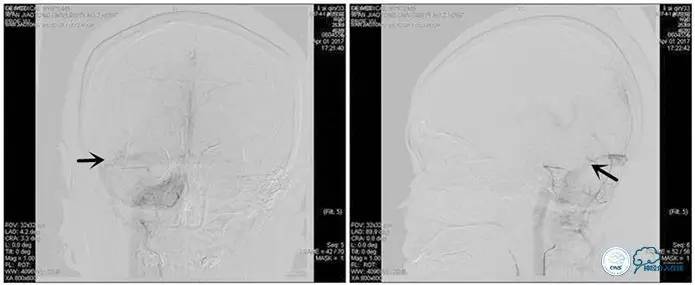

术中右侧ICA造影

右侧ICA斜位及窦内造影

右侧ICA斜位

窦内造影及路图

术中测压:

远端:520mmH2O,

近端:190mmH2O。

治疗方案:

1、8mm×40mm , EverCross球囊扩张;

2、8mm×40mm,Protégé自膨支架成形术。

术后右侧ICA造影

术后远、近端压力差为:0

术后右侧ICA斜位